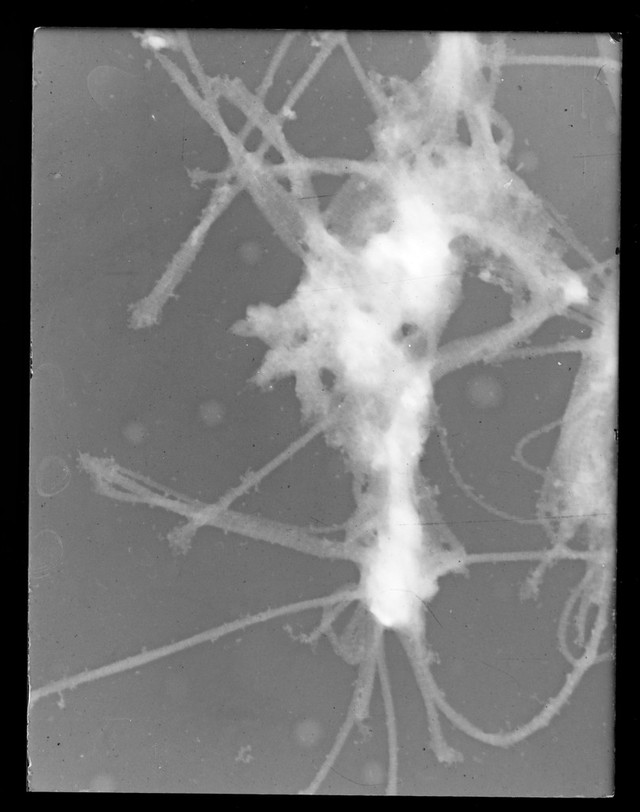

Microscope image referenced as "Angelica ganglion"

Credit: Microscope image referenced as "Angelica ganglion". Source: Wellcome Collection.